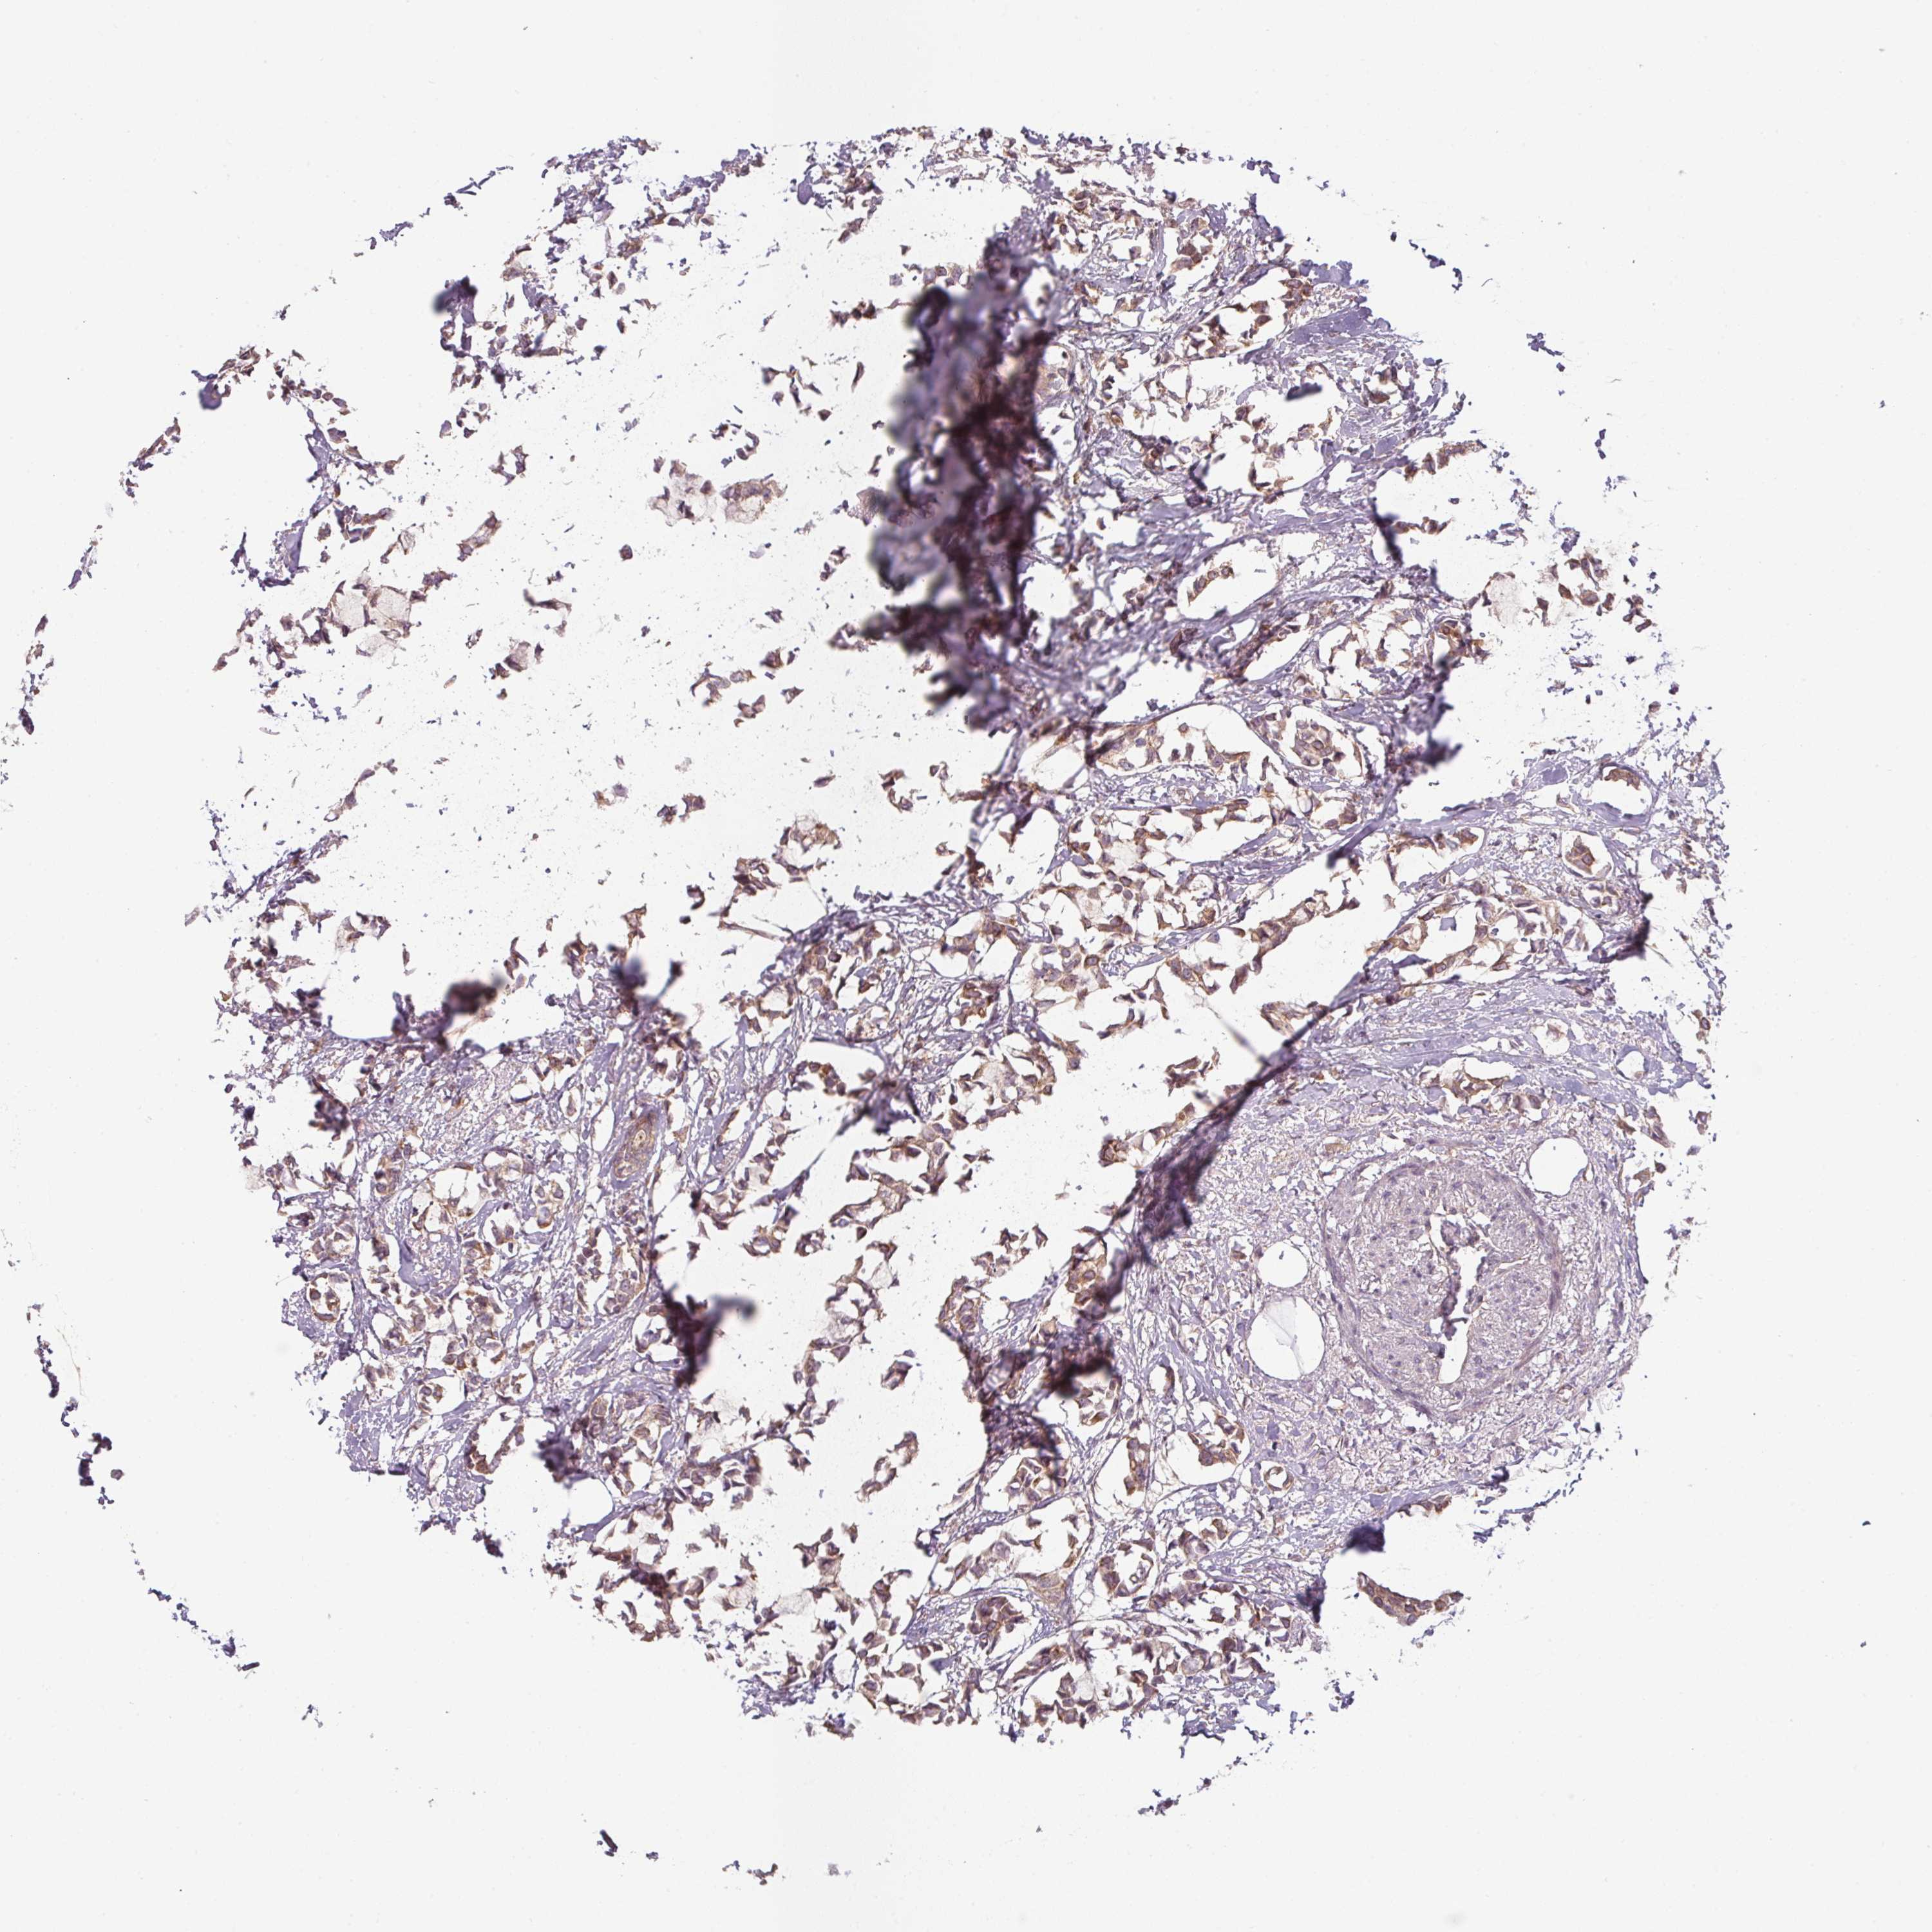

BRCA TCGA BRCA VALIDATION PROTEIN EXPRESSION